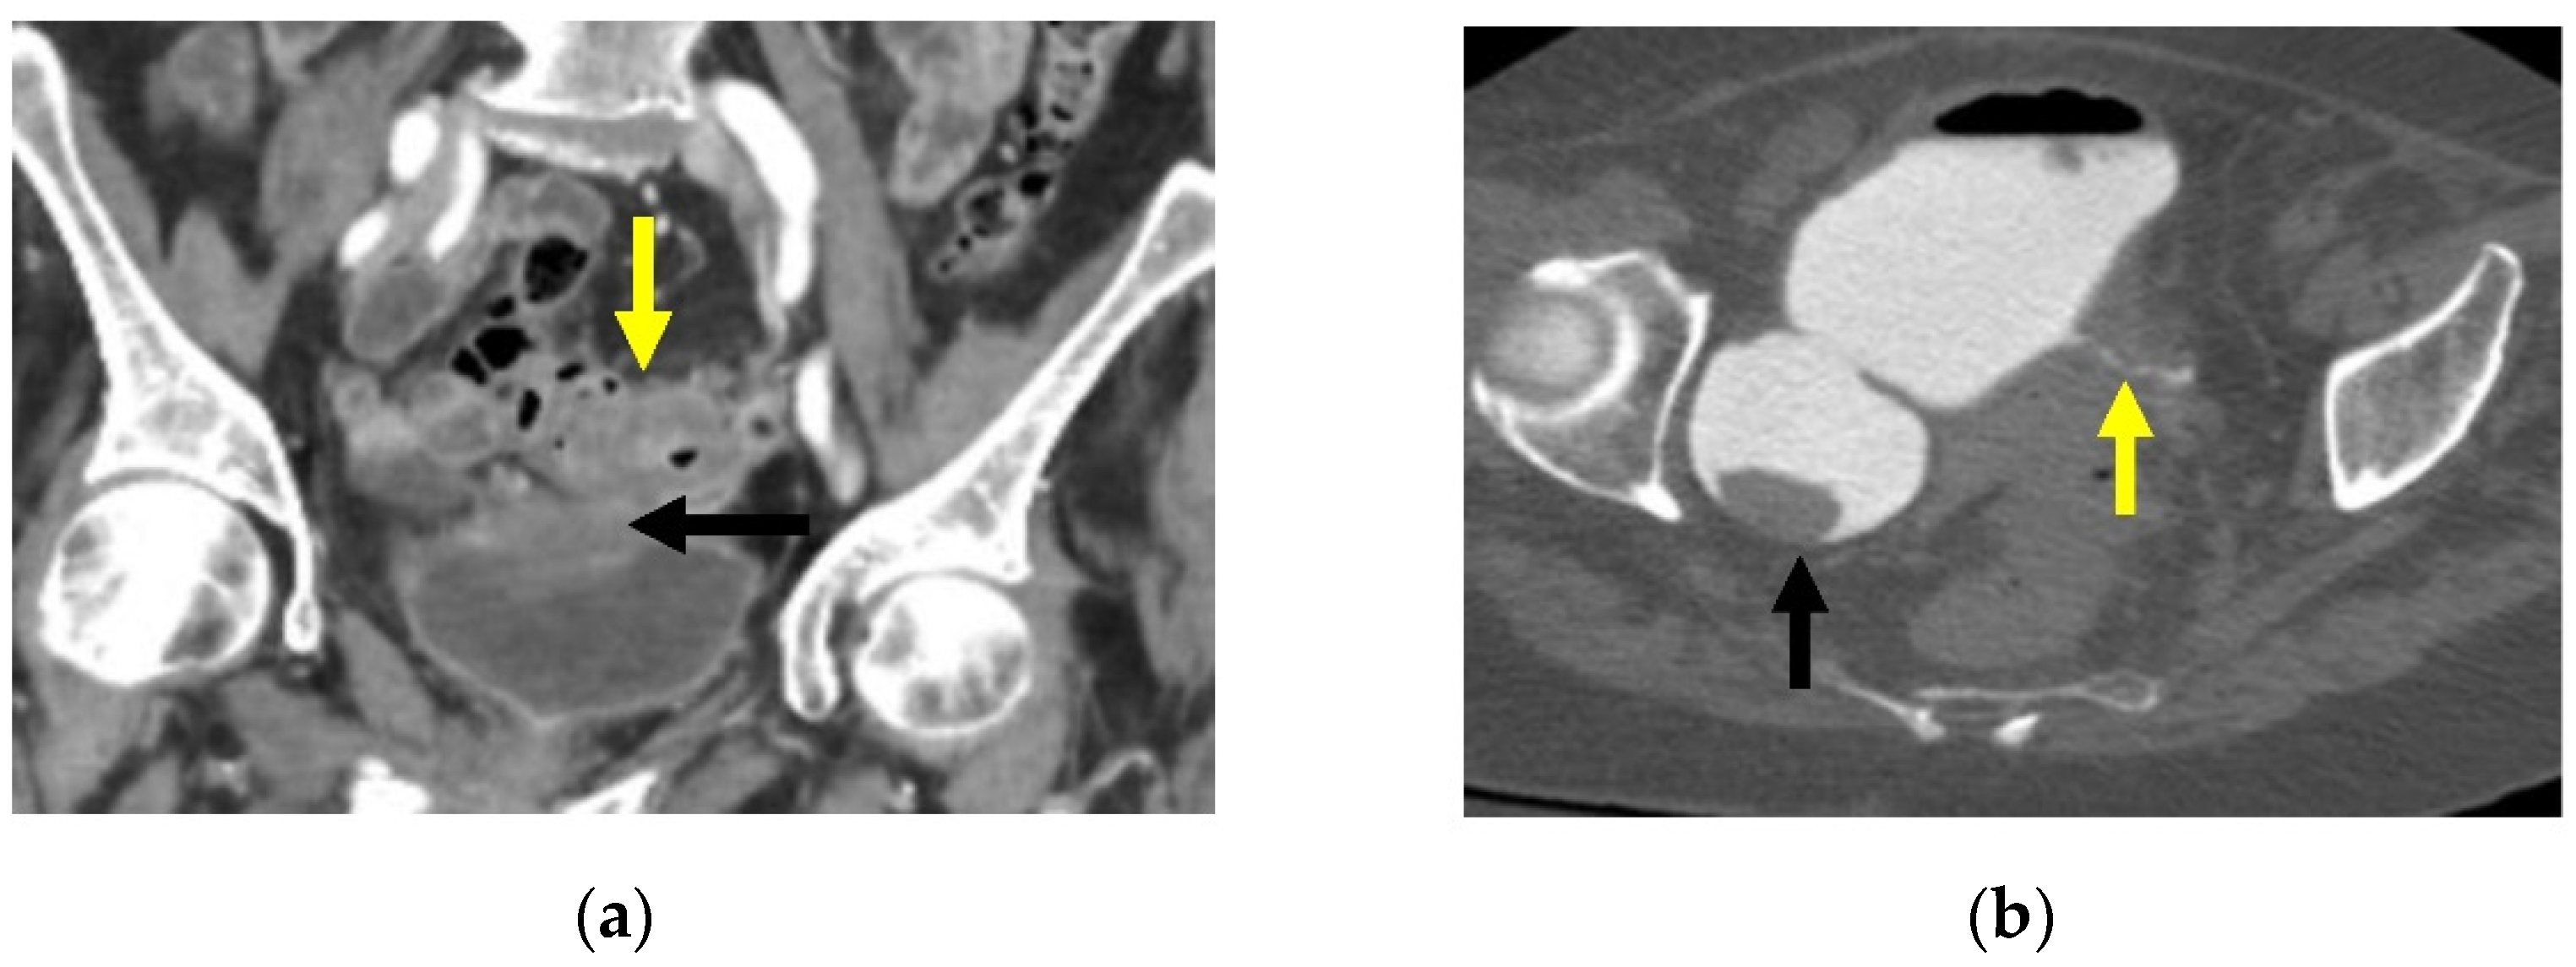

- Minordi, L.M.; Larosa, L.; Berte, G.; Pecere, S.; Manfredi, R. CT of the acute colonic diverticulitis: A pictorial essay. Diagn. Interv. Radiol. 2020, 26, 546–551. [Google Scholar] [CrossRef] [PubMed]

| Hinchey Classification [28] | Modified Hinchey Classification [4,29,31] |

| I—Pericolic abscess or phlegmon | Ia—Confined pericolic abscess |

| Ib—Confined pericolic phlegmon | |

| II—Pelvic, abdominal, or retroperitoneal abscess | II—Distant pelvic, intra-abdominal, or retroperitoneal abscess |

| III—Generalized purulent peritonitis | III—Generalized purulent peritonitis |

| IV—Generalized fecal peritonitis | IV—Fecal peritonitis |